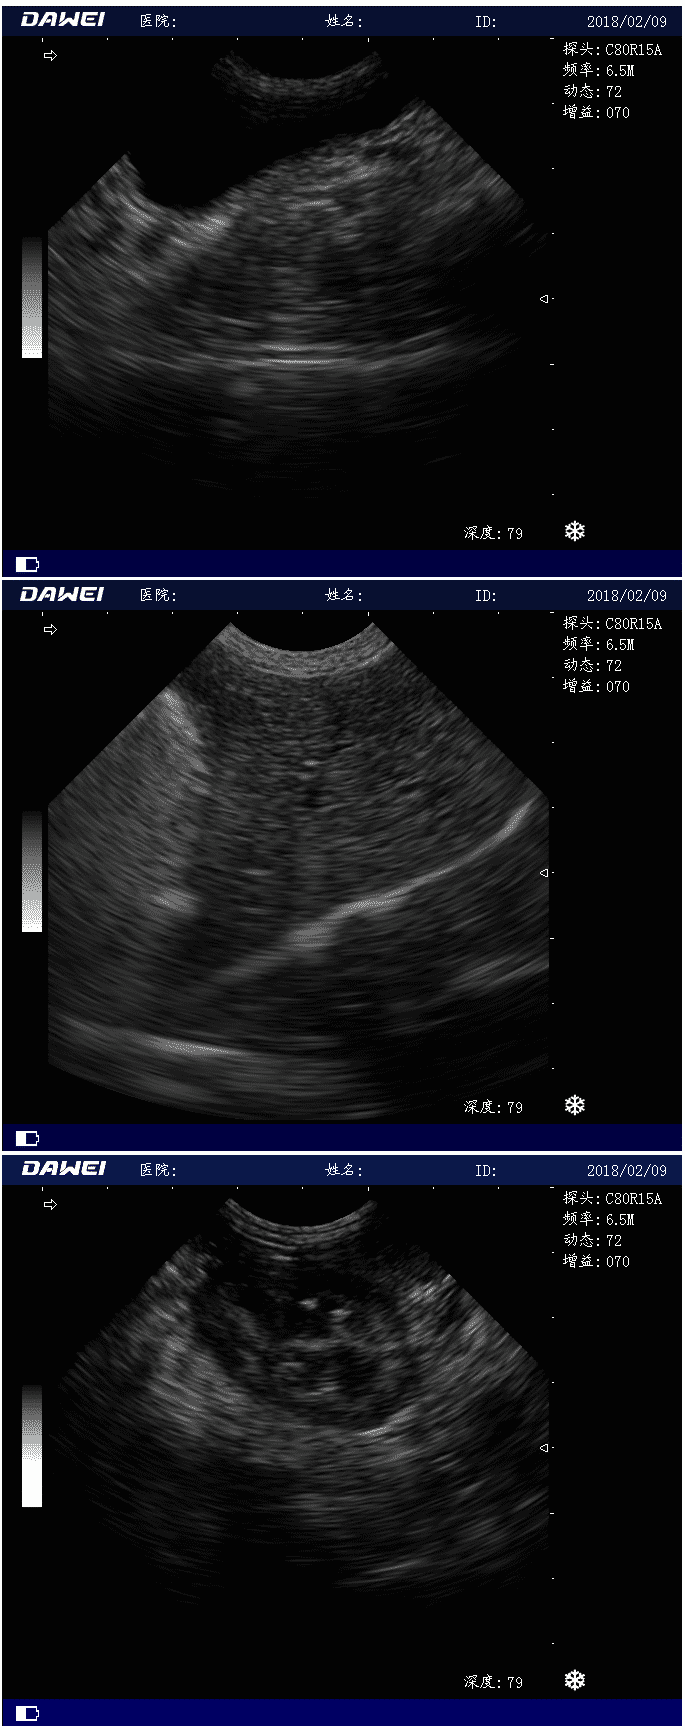

MT15獸用B超機檢測圖